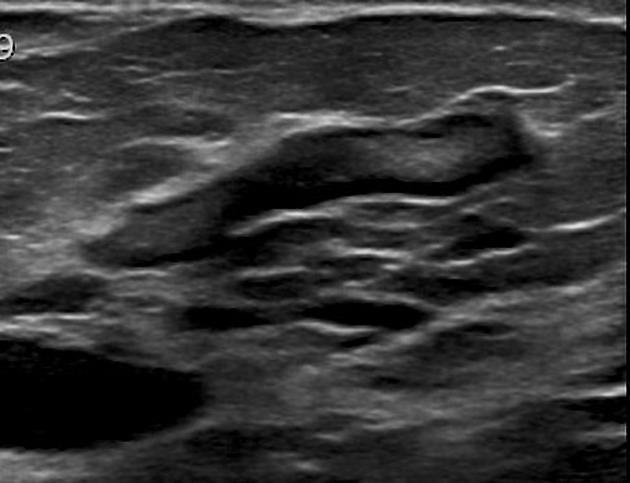

Case:

Ultrasound revealed an irregular hypoechoic lesion of 3 cm, with marked posterior acoustic shadowing (the lesion was considered as BI-RADS 5).

Echo color Doppler shows a peripheral straight vessel penetrating the lesion, but no internal vessels.